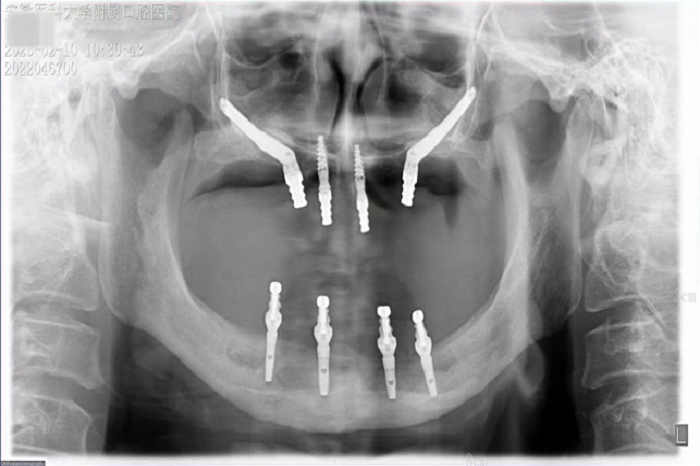

2月8日,91国产 种植科主任刘鑫带领其团队完成一例上颌骨“穿颧”、下颌神经游离种植手术。该手术是继2019年种植科完成首例穿颧种植术后的第二例穿颧种植。

据悉,患者潘女士54岁,由于重度牙周炎导致全口牙齿缺失,严重影响面容及咀嚼功能,因颌骨严重萎缩无法进行活动义齿修复,遂来91国产 种植科要求行上颌稳固的修复。通过检查发现潘女士上下颌骨骨量严重不足,经反复比对和考量,刘鑫主任制定了对患者上颌骨进行穿颧种植修复、下颌骨通过神经游离进行种植的方案。经过患者与家属深思熟虑后,接受了行穿颧种植术的建议。治疗组通过专业三维设计软件规划植体,口腔颌面外科和种植科专家共同完成了穿颧种植手术。患者术后第一天情况良好,无明显肿胀,精神状态佳。